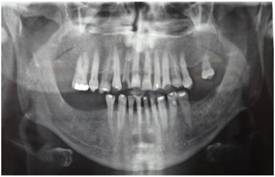

Clinical report: A 52-year-old man was presented to our department complaining that he was not satisfied with the appearance of his teeth; his teeth showed progressive wear and he had problems speaking and chewing (Fig.1).

The patient reported that he had previous pocket surgery in both jaws and that some of his teeth had been extracted because of extensive caries and periodontitis. He also mentioned that he had endodontic treatment and amalgam and composite restorations in some teeth because of caries or attrition (Figs. 2 and 3).

The clinical examination revealed attritional facets on the anterior teeth and premolars in both jaws. There were multiple abfractions and caries in cervical surface of the remaining teeth. The patient had a loss of VDO because of severe attrition. The maxillary left second premolar and molar teeth had an unfavorable crown–root ratio and furcation involvement (Fig.4).

The anterior and posterior occlusal planes were uneven because of supra-eruption and the drifting of the remaining teeth into the edentulous areas. The occlusal examination revealed destructive non-working side contacts.

The severe wear was attributed to long-term posterior edentulism, supra-eruption, and the drifting of teeth into the adjacent and opposing edentulous areas, which resulted in premature contact and bruxism. The wear was intensified following the exposure of dentin and the progression of periodontal disease. Tooth mobility further aggravated the malocclusion. The poor oral hygiene practices resulted in multiple cervical caries. Our patient was assigned to the third category in the Turner and Missirlian6 classification for patients with extensively worn dentition (Table 1).